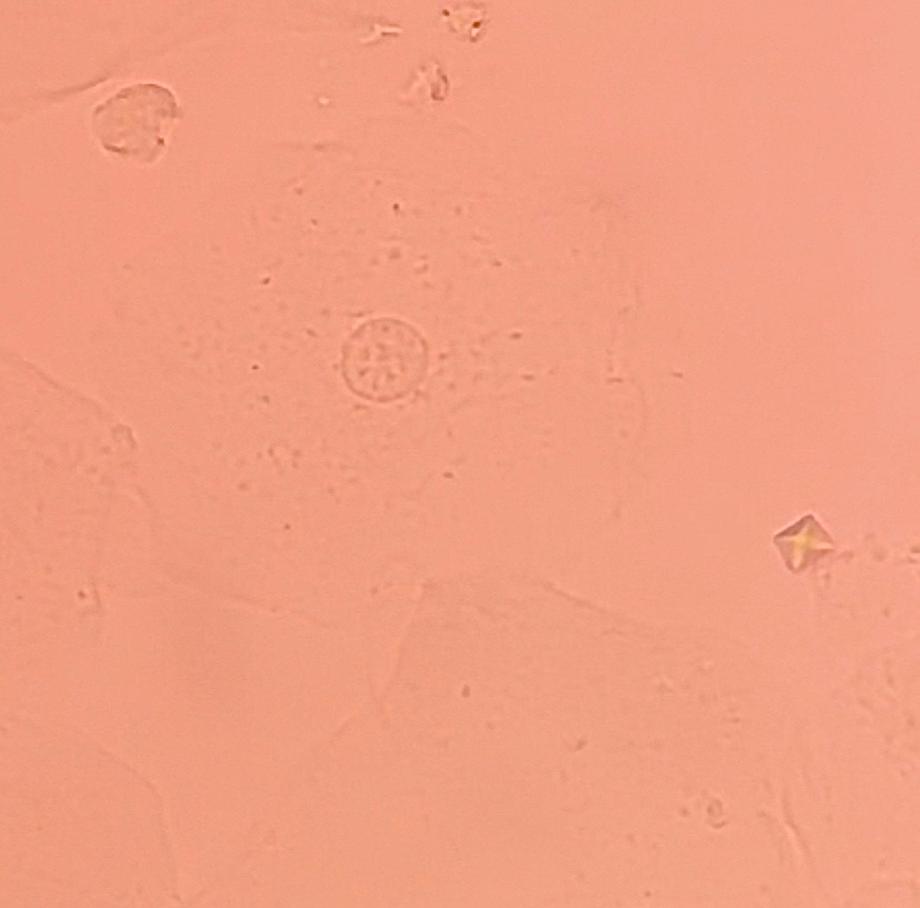

본문 시작 요 pH 측정 임상병리학과 388 2025-05-19 요 pH를 측정해본 후 산성뇨, 염기성뇨와 관련된 질병에 대해 알아보는 시간을 가졌습니다 목록 이전요시험지 테스트 다음 환자 검체를 이용한 요침사 검경 & 회식 만족도조사 만족도 조사 이 페이지에서 제공하는 정보에 대하여 만족하시나요? 매우만족 만족 보통 불만족 매우불만족